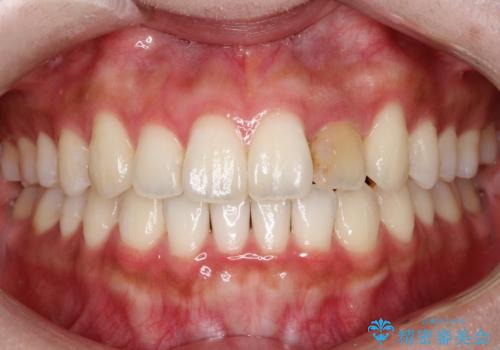

前歯の変色 オールセラミッククラウン

- 前歯の変色を主訴に来院されました。

根管治療後、オールセラミッククラウン(エクセレント)にて治療を行なっています。